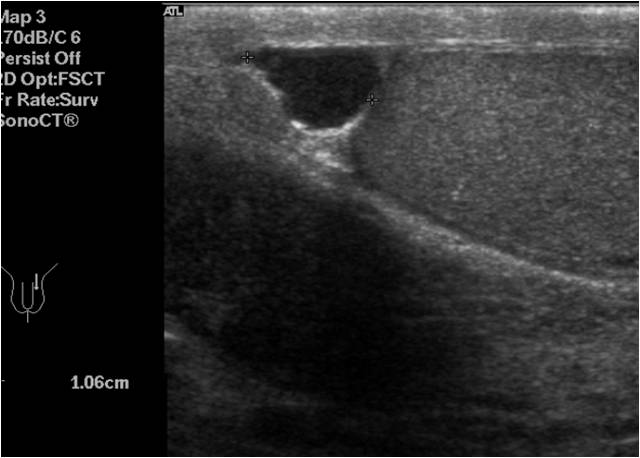

Buscamos como referencia siempre el Músculo Pronador Cuadrado. En corte AXIAL. Ecográficamente alargado, profundo, hipoecogénico, anterior a Radio y Cúbito.

Arteria Radial, anecoica, flanqueda por dos venas, que son anecoicas, más pequeñas y depresibles.

Profundo y más medial el Flexor del Pulgar, mueve el pulgar y vas a ver como se mueve el tendón, infalible si tienes dudas de cual es. Es hiperecogénico con halo hipoecogénico y casi redondo.

Más superficial, más ovalado el Tendón Flexor Radial del Carpo. Ecográficamente hiperecogénico.

Un poco más medial, otras dos estrecturas, el Nervio Mediano, más profundo , aunque luego se hace superficial.

Más superficial, el tendón del palmar largo. Ten cuidado de no comprimir en exceso porque lo perderás de la visión.